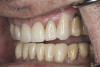

(35.) Postoperative right lateral, closed view.

Figure 35